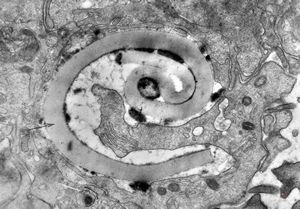

M,33y. | blood - hairy cell leukemia- ribosome-lamella complexin tricholeukocyte